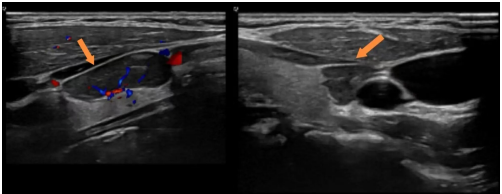

超声科主治医师谭庆亭执行甲状腺超声检查时,发现患者左叶外侧有一个低回声结节,位置有些“尴尬”——既不像典型的甲状腺结节,也不在正常甲状旁腺的解剖区域,于是在报告中审慎写道:“甲状腺来源可能性大,其他来源不除外。

看到这句超声诊断,刘安阳立刻意识到这背后谨慎的留白。他打开超声图像仔细查看:结节回声均匀,包膜完整,血供丰富,与甲状腺相对独立,虽然也确实不在典型旁腺位置,但“不除外”三个字,已是最重要的提示。刘安阳随即为患者开具针对性检查,结果迅速印证了判断:

生化指标明确指向“原发性甲状旁腺功能亢进”,结合超声特征,该结节高度考虑为异位于甲状腺区域的甲状旁腺瘤。事后交流时,谭庆亭说:“当时确实很纠结,位置太不典型,直接下旁腺诊断依据也不充分。”刘安阳回应:“你写的‘不除外’,就是给我最重要的线索。如果只报‘甲状腺良性结节’,这个甲旁亢很可能就错过了。”